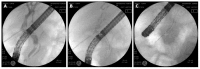

Methods: Five cases operated on for CBDSs and having retained stones with a T-tube were referred from other hospitals located in or around Istanbul city to the ERCP unit at the Haydarpasa Numune Education and Research Hospital. Under sedation anesthesia, a sterile guide-wire was inserted via the T-tube into the common bile duct (CBD) then to the papilla. A guide-wire was held by a loop snare and removed through the mouth. The guide-wire was inserted into the sphincterotome via the duodenoscope from the tip to the handle. The duodenoscope was inserted down to the duodenum with a sphincterotome and a guide-wire in the working channel. With the guidance of a guide-wire, the ERCP and sphincterotomy were successfully performed, the guide-wire was removed from the T-tube, the stones were removed and the CBD was reexamined for retained stones by contrast.

Conclusion: The modified Rendezvous technique is a very easy method and increases the success of postoperative ERCP, especially in patients with large duodenal diverticula and with intradiverticular papilla.